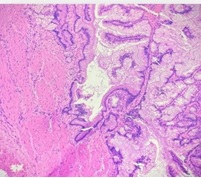

Case Presentation: A 48-year-old female presented with complaints of vague upper abdominal pain for last 10 days.Ultrasound abdomen revealed polypoidal mass filling gall bladder lumen measuring 7x3.8 cm. MRCP revealed hypointense mass lesion within gallbladder lumen with its stalk at the hepatic surface of gall bladder. CT abdomen revealed heterogeneously enhancing gall bladder mass with no regional lymphadenopathy. Serum tumor markers of CEA, CA19.9 were normal. Patient underwent en bloc resection of 2 cm segment IVB liver along with gallbladder. Intraoperative frozen section specimen revealed exophytic polypoidal papillary lesion in distal body of gallbladder measuring 5x4x3 cm. Microscopic features revealed intracholecystic papillary neoplasia with low-grade dysplasia. Regional lymphadenectomy was not performed. Final diagnosis of Intracholecystic papillary neoplasm,gastric type was confirmed and patient was kept on close follow up.

Conclusion: Intracholecystic papillary neoplasm of gall bladder is a rare entity presenting as intraluminal growth which require proper histopathological diagnosis. Clinical features and imaging modalities are non-specific. They have variable morphological subtypes like papillary or tubular growth patterns and may have underlying varying degree of dysplasia or invasive foci making it pertinent to perform surgical resection.They are relatively indolent with better prognosis as compared to gallbladder carcinomas. Further studies are required to precisely diagnose it and manage the various subtypes appropriately.